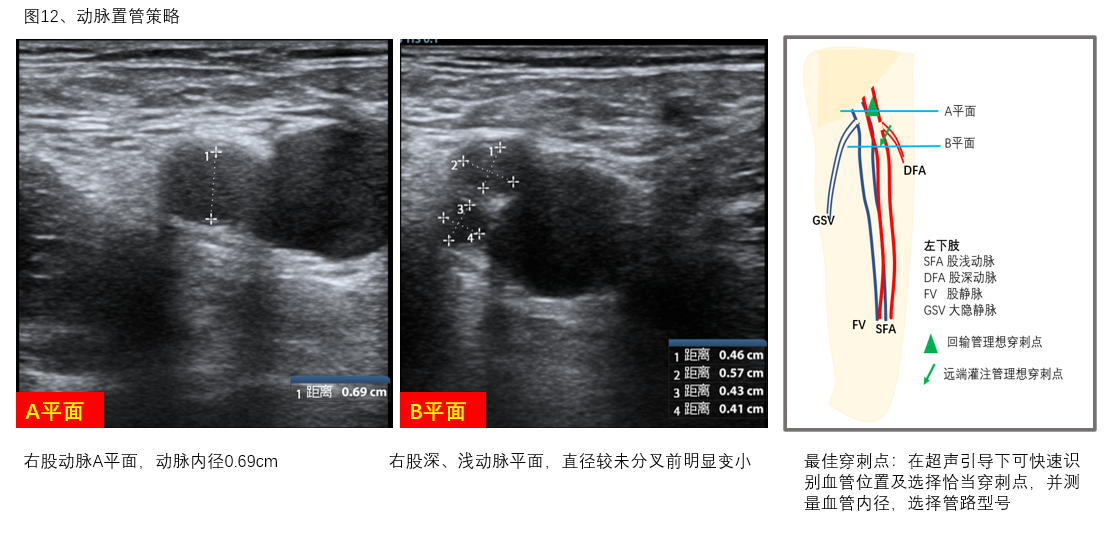

C、动脉直径:测量拟置管动脉血管的内径,选择合适的动脉管路型号,并可根据血管内径与拟置入管路外径之间的大小关系预估肢体远端肢体缺血可能,评估远端灌注管放置必要性,并可根据血管具体情况预估置管困难程度制定置管策略,如经皮穿刺、半切开、切开等,做好置管预案(图12)。

图12